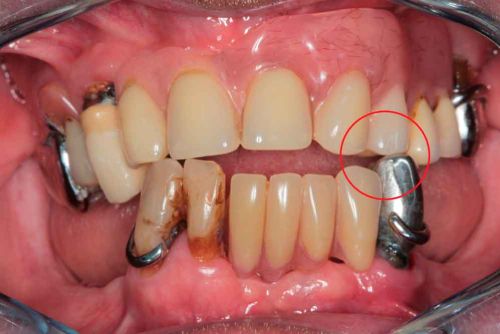

66 years old patient. Wishes to regain functional comfort and improve aesthetics.

Complaints :

- Lack of stability of his removable prosthetics

- Difficulties in eating

- Sagging of the upper lip

The periodontal structures of the remaining teeth are no longer sufficient. An edentulism is considered. The treatment plan is directed towards a removable maxillary complete prosthesis and an implant-supported mandibular complete prosthesis.

Picture - Initial bite situation